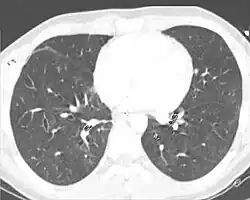

A chest CT scan revealing pulmonary contusions, pneumothorax, and pseudocysts

Computed tomography (CT scanning) is a more sensitive test for pulmonary contusion,[8][38] and it can identify abdominal, chest, or other injuries that accompany the contusion.[43] In one study, chest X-ray detected pulmonary contusions in 16.3% of people with serious blunt trauma, while CT detected them in 31.2% of the same people.[50] Unlike X-ray, CT scanning can detect the contusion almost immediately after the injury.[48] However, in both X-ray and CT a contusion may become more visible over the first 24–48 hours after trauma as bleeding and edema into lung tissues progress.[51] CT scanning also helps determine the size of a contusion, which is useful in determining whether a patient needs mechanical ventilation; a larger volume of contused lung on CT scan is associated with an increased likelihood that ventilation will be needed.[48] CT scans also help differentiate between contusion and pulmonary hematoma, which may be difficult to tell apart otherwise.[52] However, pulmonary contusions that are visible on CT but not chest X-ray are usually not severe enough to affect outcome or treatment.[42]